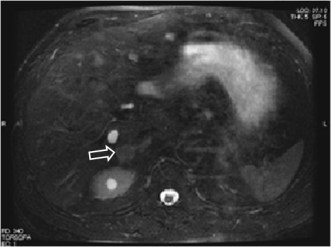

SIGNO DEL ANILLO HIPERINTENSO (en el adenoma suprarrenal)

Signo de adenoma suprarrenal en Resonancia magnética, en imágenes spin-echo con saturación de grasa. Corresponde a un anillo hiperintenso que rodea la masa suprarrenal y que puede tratarse de la cápsula tumoral o del tejido sano comprimido periféricamente. Este signo permite distinguir adenomas de metástasis, que no muestran el anillo.

Más información en: Tomoaki Ichikawa. Adrenal adenomas: characteristic hyperintense rim sign on fat-saturated spin- echo MR images. Radiology 1994; 193: 247-250.